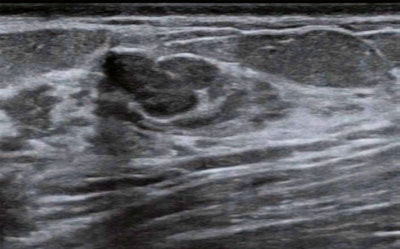

Cui and colleagues sought to explore the impact of deep learning-based CAD software on the diagnostic performance of radiologists without such expertise; they also tested the software at secondary and rural hospitals. The investigators asked radiologists participating in the study to differentiate between benign and malignant by assigning a BI-RADS category for breast lesions measuring up to 2 cm on ultrasound.

The study included 313 women with 313 breast lesions. Of these lesions, 102 were malignant and 211 were benign.

Cui and colleagues found that CAD downgraded 79.1% of BI-RADS 4a lesions to BI-RADS 3 and upgraded 6% of BI-RADS 3 lesions to BI-RADS 4a.